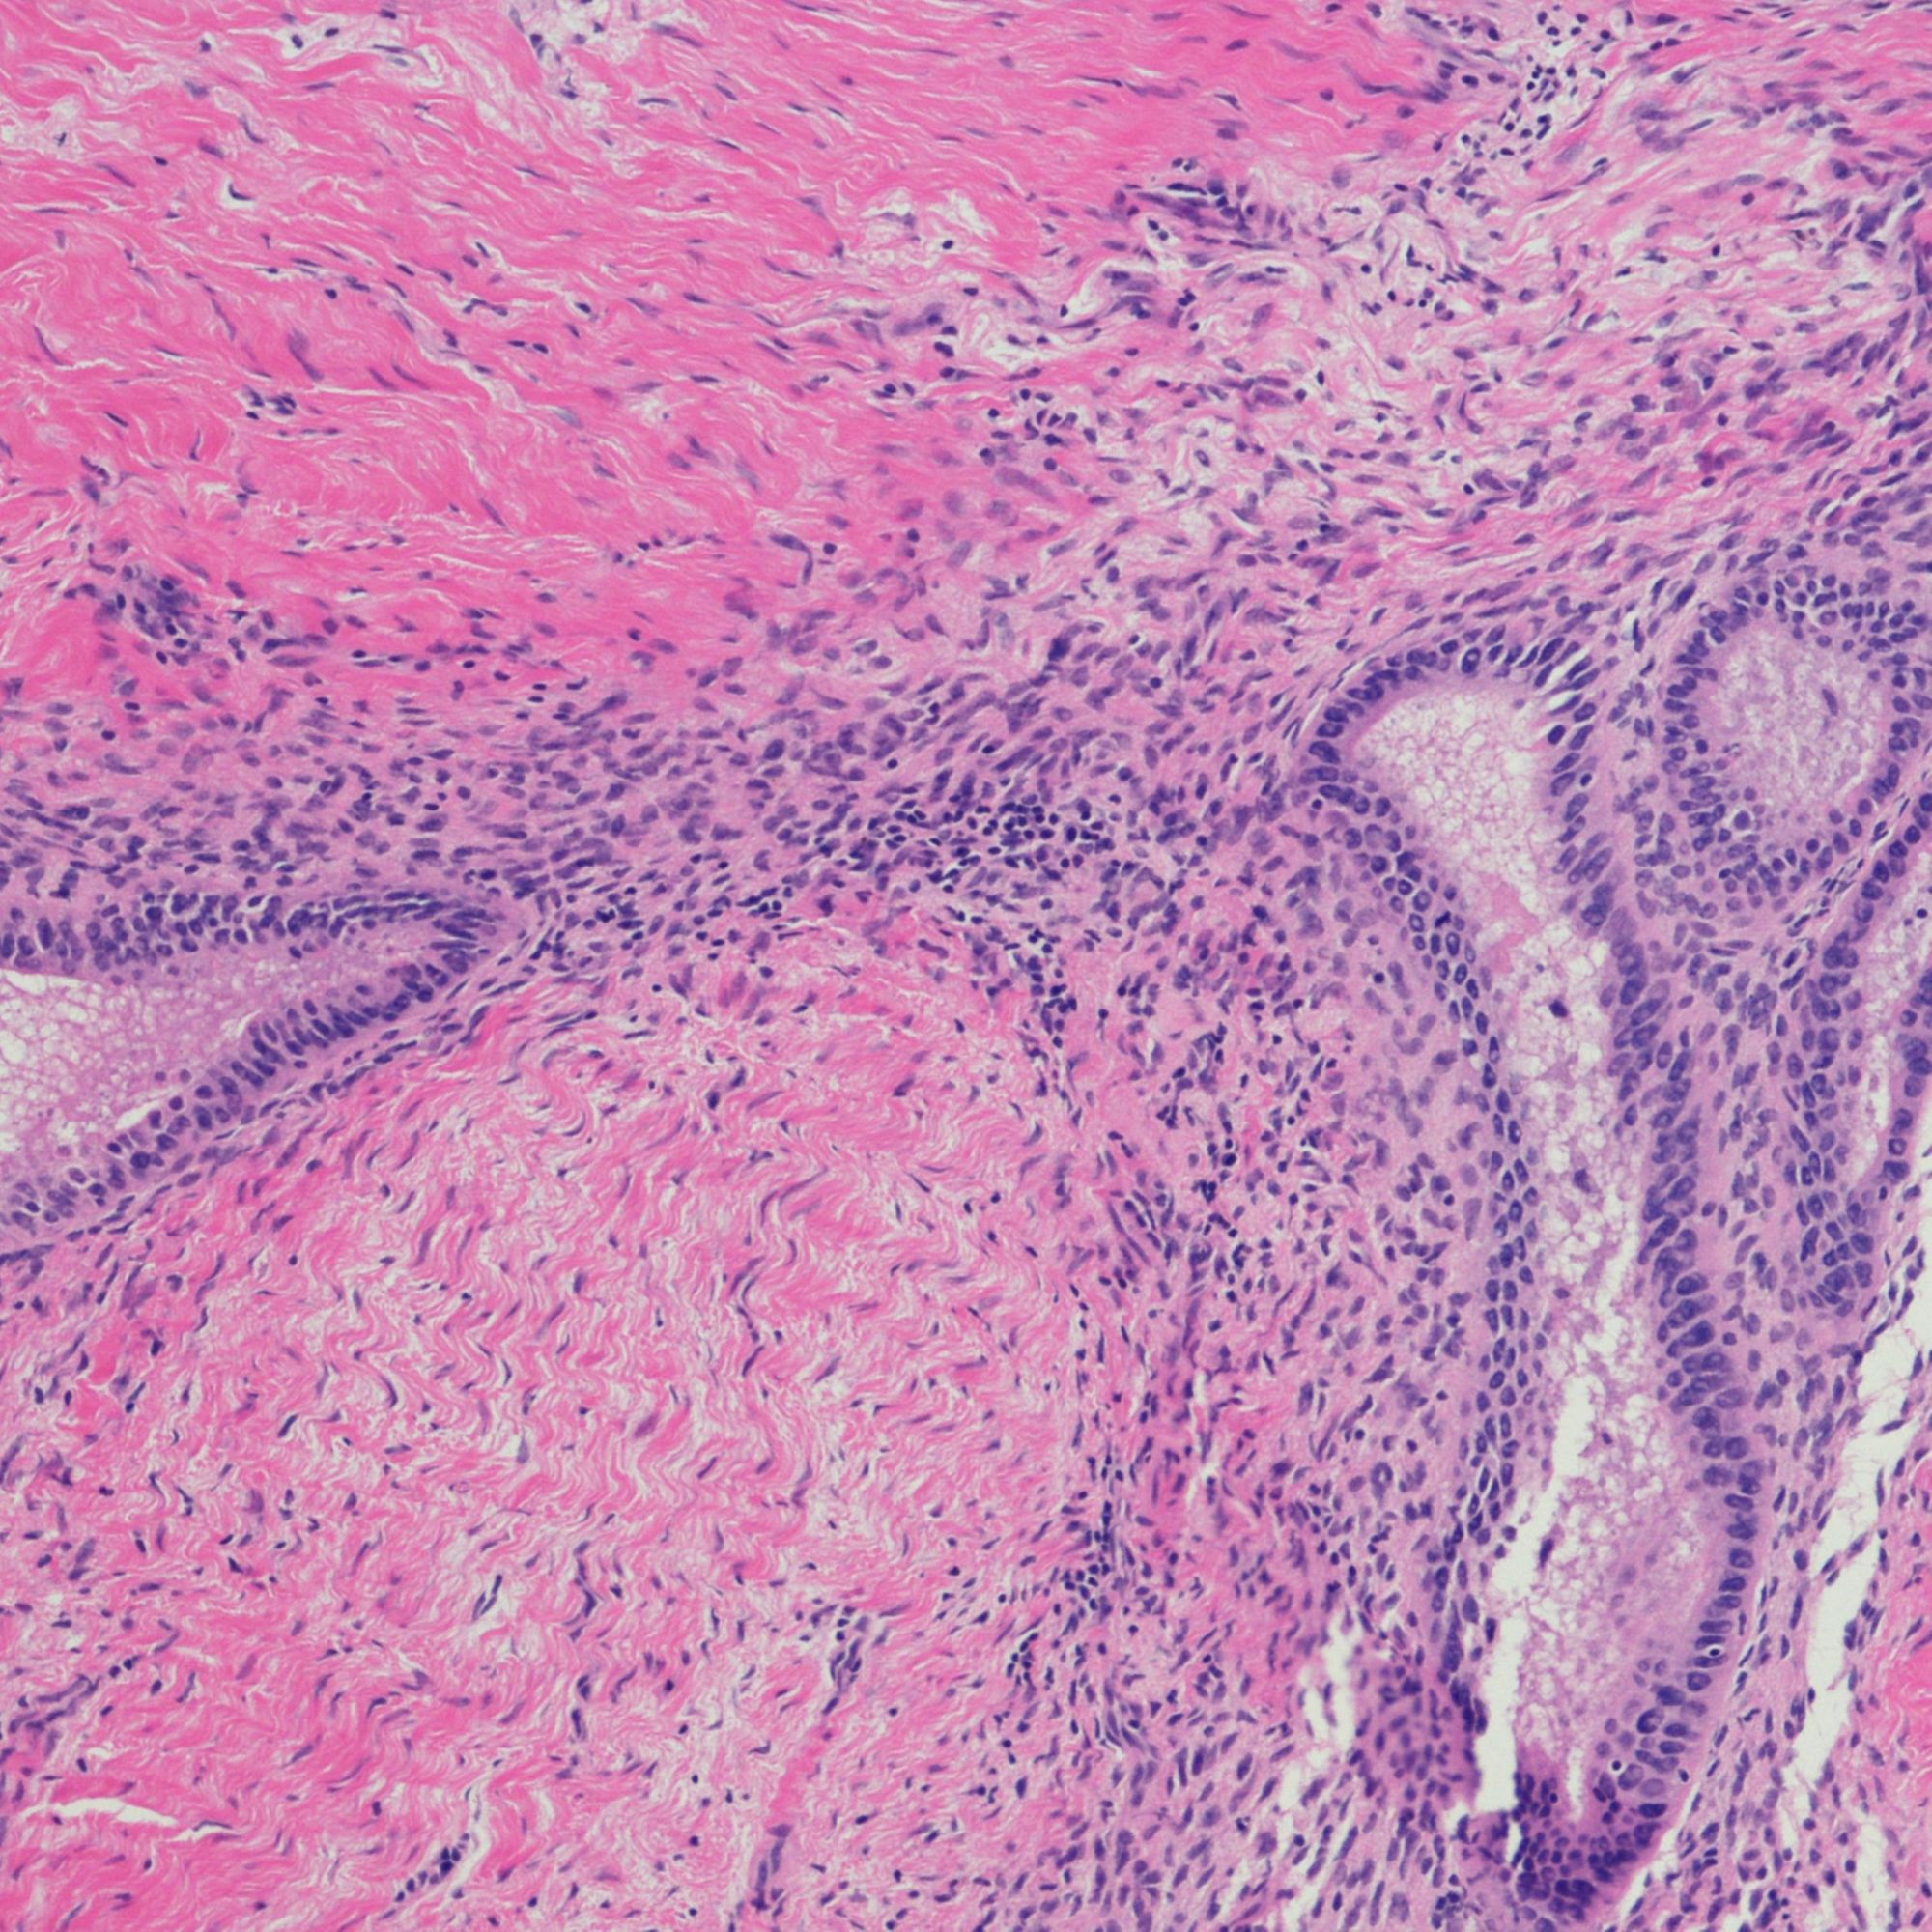

L’endométriose est une maladie gynécologique chronique de la femme en âge de procréer. Sur le plan médical, elle se caractérise par la présence anormale d’endomètre en dehors de la cavité utérine. L’endomètre constitue la muqueuse utérine, c’est-à-dire la couche la plus interne de l’utérus. Au terme du cycle menstruel, une grande partie de l’endomètre est censé être éliminé lors des règles. Dans le cas de l’endométriose, ce tissu situé en dehors de la cavité utérine demeure après les règles, et réagit aux variations hormonales du cycle menstruel. Cela provoque aux endroits où il se trouve des saignements, des nodules, des kystes, ainsi que des inflammations et des formations de tissus cicatriciels pouvant toucher les organes avoisinants. Ses causes sont encore trop mal connues, multifactorielles, associant des facteurs directement liés aux menstruations à des facteurs génétiques et environnementaux.